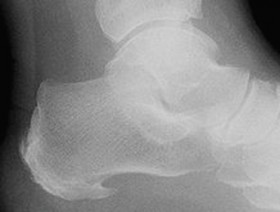

There are many causes of heel pain:

Plantar Fasciitis – Heel Spur – Achilles Tendinosis – Bursitis – Nerve Entrapment Syndrome

Wastage of Fat Pad of Heel – Stress Fracture – Sever’s Disease – Gout – Ankylosing Spondylitis – Footwear